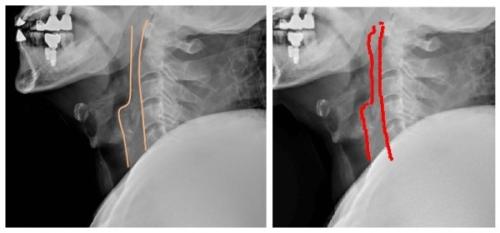

¿Ü»óÀ¸·Î ÀÀ±Þ½ÇÀ» ¹æ¹®ÇÑ È¯ÀÚ¿¡¼ °æÃß¿Í ÈäºÎ, °ñ¹Ý X-ray¸¦ ±âº»À¸·Î ÃÔ¿µÇØ »óŸ¦ È®ÀÎÇÑ´Ù. ÀÌ Áß °æÃß X-ray ¿µ»óÀº ÀÀ±ÞȯÀÚ³ª ÁßÁõ ȯÀÚ¸¦ Æò°¡Çϴµ¥ Áß¿äÇÑ ±âÃÊ ¿µ»óÀÚ·á·Î Ȱ¿ëµÈ´Ù.

°æÃß C2/3¹ø°ú C6/7¹øÀÇ °æ¿ì ôÃß¾Õ°ø°£Àº °¢°¢ 6~7mm¿Í 20mm Á¤µµ·Î ÃøÁ¤µÇ´Âµ¥, ³»ºÎÃâÇ÷À̳ª ºÎÁ¾ µîÀÌ ÀÖÀ» °æ¿ì ÀÌ µÎ²²°¡ ³Ð¾îÁø´Ù. ÀÌ ¶§ ÀÇ»ç´Â X-ray ¿µ»óÆÇµ¶°á°ú¿¡ µû¶ó CT³ª MRI µîÀÇ Á¤¹Ð °Ë»ç¸¦ ½Å¼ÓÈ÷ ÁøÇàÇØ¾ß ÇÒÁö ÀÀ±Þóġ¸¦ ¿ì¼±ÇØ¾ß ÇÒÁö µîÀÇ Áø´Ü°ú Ä¡·á °èȹÀ» ¼¼¿ì°Ô µÈ´Ù.

ÀÌ¿µÇÑ ±³¼ö ¿¬±¸ÆÀÀº °æÃß X-ray °Ë»ç¿¡¼ C2¹ø°ú C6¹ø ôÃß¾Õ °ø°£À» °ËÃâÇÒ ¼ö ÀÖµµ·Ï 200¸íÀÇ ÃøÁ¤°ªÀ» µ¥ÀÌÅÍÈ ½ÃÄÑ µö·¯´×À» ÅëÇØ AI¿¡ ÇнÀ½ÃÄ×´Ù.

¿¬±¸ÆÀÀº ÀÌ·¸°Ô ÇнÀÇÑ AI¸¦ ÅëÇØ ½ÇÁ¦ ÀÀ±Þ½ÇÀ» ¹æ¹®ÇÑ 136¸íÀÇ °æÃß X-ray¸¦ ºÐ¼®Çß´Ù. ºÐ¼® °á°ú C2ÀÇ °æ¿ì 132¸í(97%)¿¡¼ ¿µ»óÀÇÇаú ÀÇ»çÀÇ Áø´Ü°ú ÀÏÄ¡ÇßÀ¸¸ç, C6ÀÇ °æ¿ì 126¸í(92.7%)¿¡¼ Á¤È®µµ¸¦ º¸¿´´Ù. ƯÈ÷, °æÃß ¼ö¼úÀ» ¹ÞÀº ȯÀÚ³ª ÀÓÇöõÆ® µî º¸Ã¶¹°À» °¡Áø ȯÀÚ¿¡¼µµ Á¤È®ÇÑ Áø´ÜÀÌ °¡´ÉÇß´Ù.

½ÇÁ¦ Ä¡°ú º¸Ã¶Ä¡·á¸¦ ¹ÞÀº ¿Ü»óȯÀÚÀÇ °æÃß X-ray ¿µ»óÀ» ¿µ»óÀÇÇаú Àǻ簡 ÆÇµ¶(»çÁø ÁÂÃø)ÇÑ °á°ú¿Í AI°¡ ÆÇµ¶(»çÁø ¿ìÃø)ÇÑ °á°ú¸¦ ºñ±³ÇßÀ» ¶§ Å« Â÷À̸¦ º¸ÀÌÁö ¾Ê¾Ò´Ù. ¿¢½º·¹À̸¦ ÆÇµ¶ÇÒ ¶§ ôÃß ¾Õ °ø°£À» º¸±â À§ÇØ Ã´Ãß ¾Õ °ø°£¼±À» ±×¸®°Ô µÇ´Âµ¥ AI ¿ª½Ã Àǻ簡 ±×¸°°ø°£¼±°ú °°Àº ¸ð¾çÀ» ±×·È´Ù.